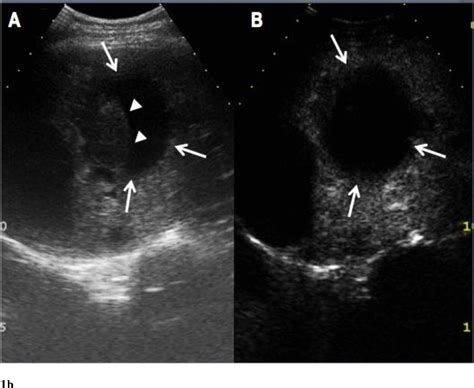

During a hepatic cyst ultrasound, several common findings may be observed:

• Simple cysts appear as well-defined, fluid-filled structures with smooth walls.

• Complex cysts may have internal septations or solid components, which can indicate a higher risk of malignancy.